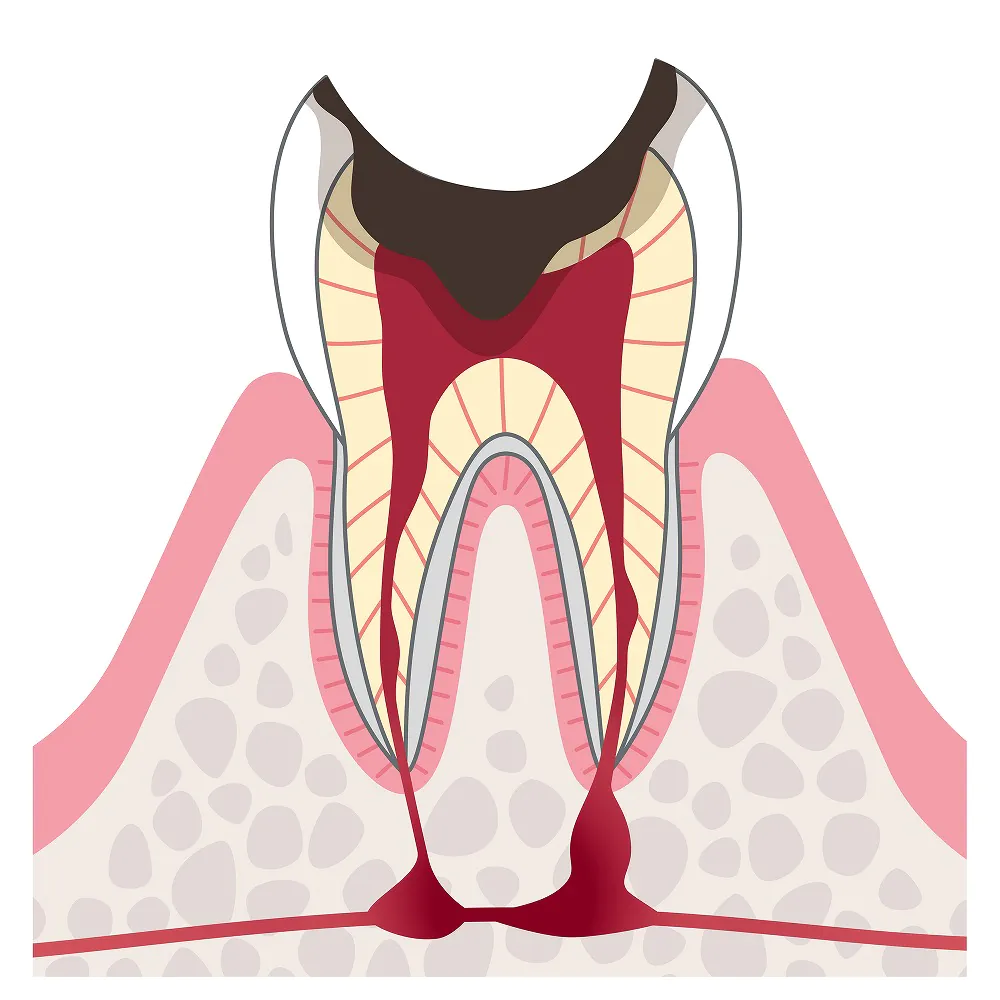

C4:歯の根だけが残った状態

歯の大部分が溶かされて、歯の根だけが残った状態です。歯の神経が壊死しているため、痛みは消失します。

歯の大部分が溶かされて、歯の根だけが残った状態です。歯の神経が壊死しているため、痛みは消失します。

しかし、歯の根の中で細菌感染が生じ、再び痛み出すことがあります。

治療法

歯の保存は困難なため、抜歯をして入れ歯やブリッジ、インプラントなどで歯の機能を補います。